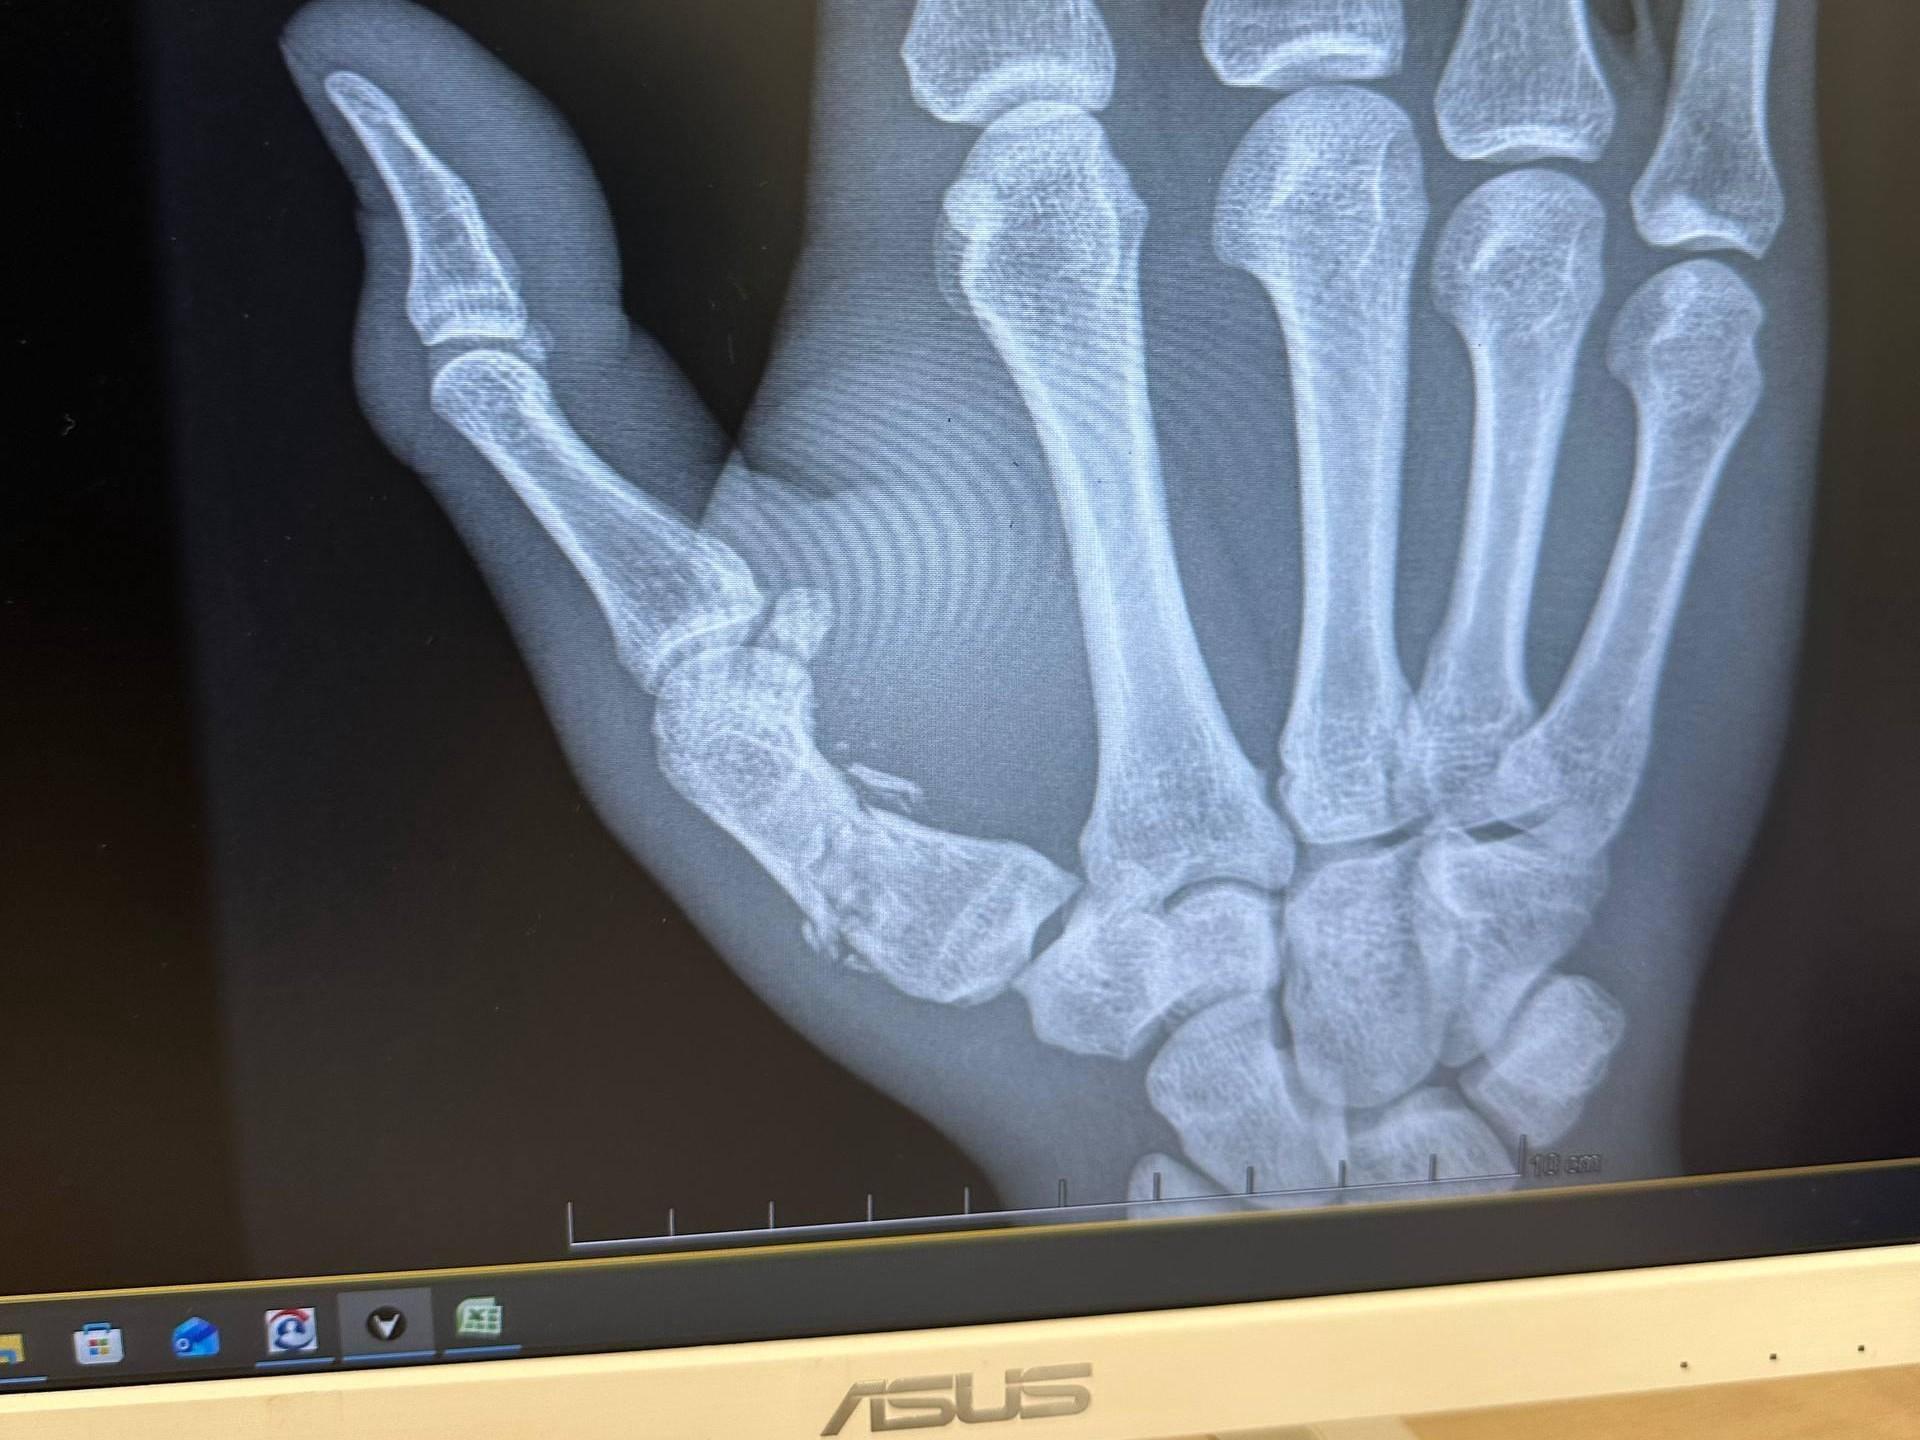

«Something like that,» Andrey wrote, attaching a photo of an X-ray.

Earlier, his cornerman Andrey Koreshkov also spoke about the injury the fighter sustained. According to him, Pulyaev broke his thumb at the very beginning of the fight but did not withdraw and spent all three rounds in the octagon.

«He broke his thumb in the first round, essentially fighting with a fracture in the second and third five-minute rounds and landing some good shots,» Metaratings.ru quotes Koreshkov as saying.